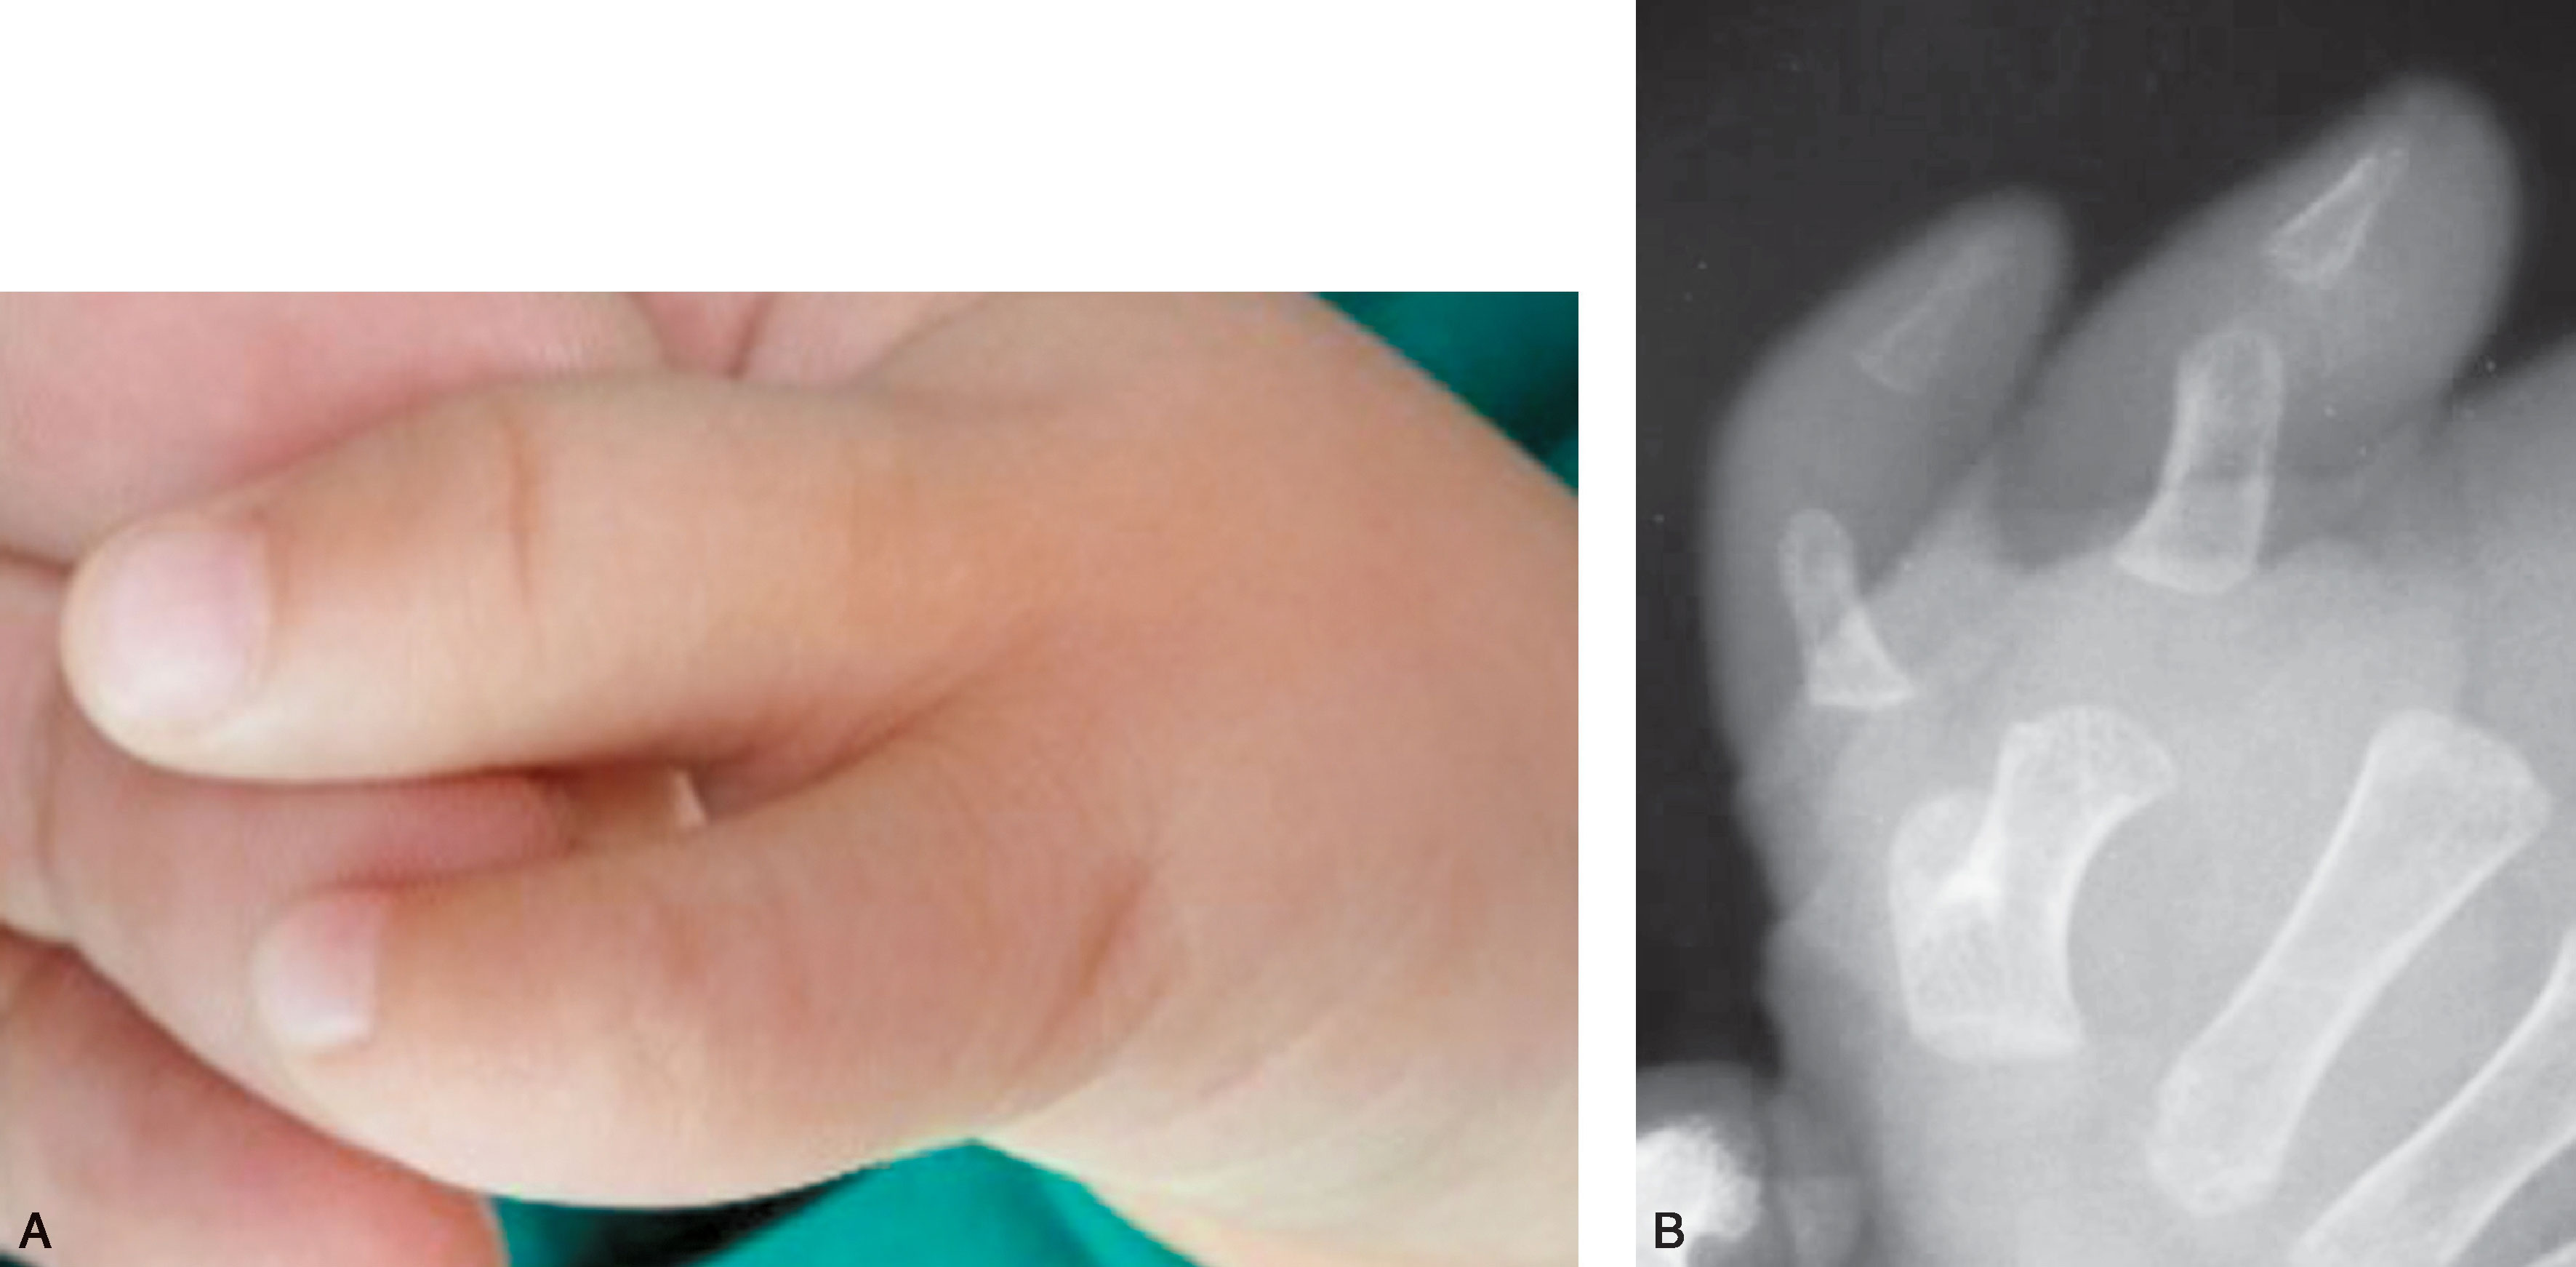

1.Ⅰ型 末节指骨未完全分裂,近节指骨正常或不正常,共用一个骨骺,并与近节指骨远端形成关节(图2-1-1~图2-1-4)。

图2-1-1 Ⅰ型病例1

A.主拇指与次拇指外形差异较大,各自有独立的指甲,远节尺偏(左侧);B.X 线片显示,虽然指骨远端分开,但基底共用一个骨骺,重建时需手术切除部分桡侧骨骺板,远节指骨尺偏需行近节指骨远端桡侧闭合楔形截骨,以纠正远节手指的尺偏畸形